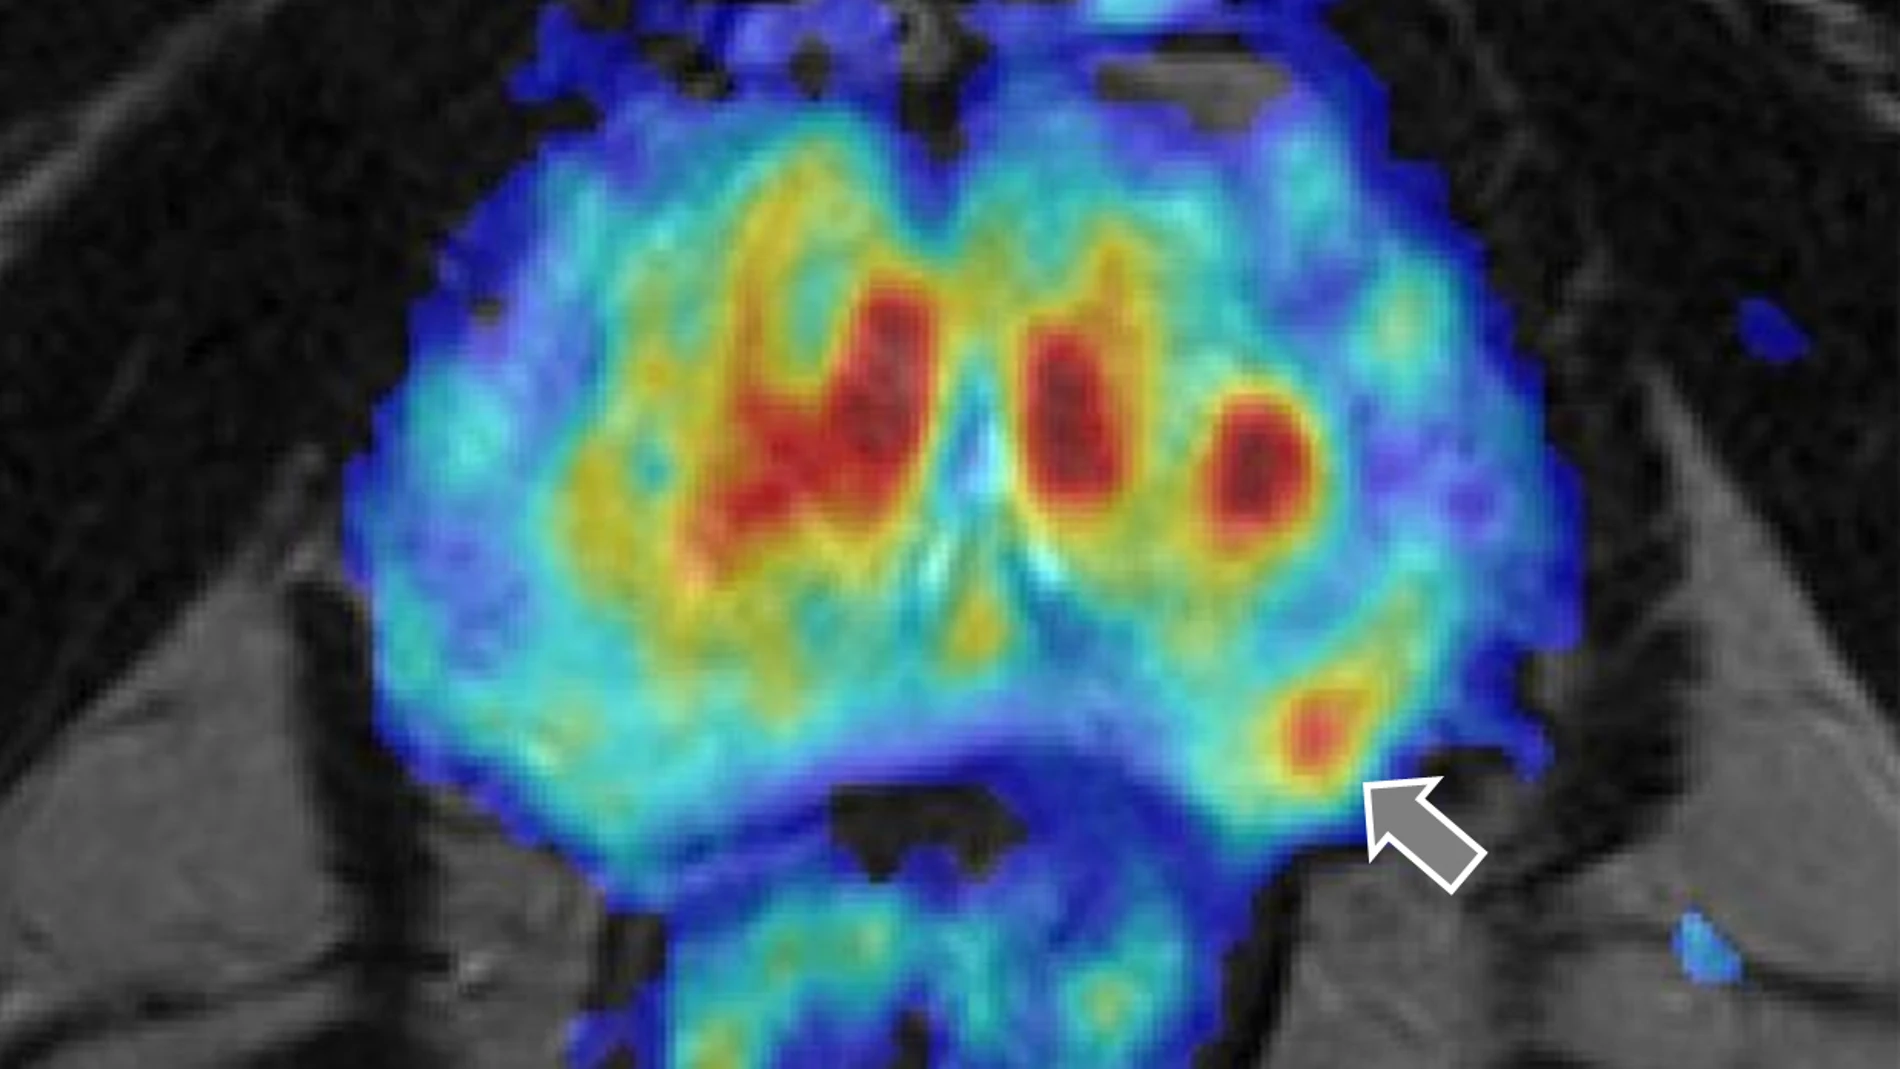

Así, cuando el problema se diagnostica a tiempo, el abanico de posibilidades que se abre resulta muy amplio e «incluye la cirugía radical, la radioterapia y la hormonoterapia, todas ellas con diferentes modalidades y siempre indicadas conforme al momento evolutivo de la enfermedad. Otras opciones contemplan la vigilancia activa y la terapia focal ablativa cuando la patología está localizada, y la quimioterapia y otras opciones dirigidas al tratamiento de la enfermad ósea cuando está más avanzada», explica Carballido.

Con un buen diagnóstico y tratamiento, la mayoría de estos pacientes tiene larga supervivencia y convive con la enfermedad con carácter crónico. Parte de ese éxito está en los avances terapéuticos que se han impuesto en los últimos años. «Destacan sobremanera el perfeccionamiento de la cirugía radical incluyendo la cirugía laparoscópica robótica, los avances en las técnicas de radioterapia externa con intensidad modulada IMRT como forma avanzada de 3D-CRT y la SBRT o la expansión de la hormonoterapia con la aparición de la moderna hormonoterapia con fármacos antagonistas del receptor androgénico. Opciones, todas ellas, que adecuadamente indicadas han contribuido a mejorar la cantidad y la calidad de vida de los pacientes con cáncer de próstata», concluye Carballido.